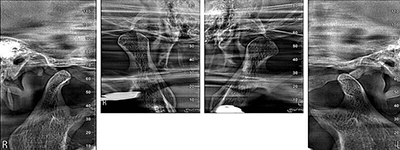

Pro Patient: Our state-of-the-art cone-beam computed tomography (CBCT) technology could selectively image the sinus, oral maxillofacial, para-nasal sinuses, ear & throat regions.

3D Imaging with Field of View sizes available in: